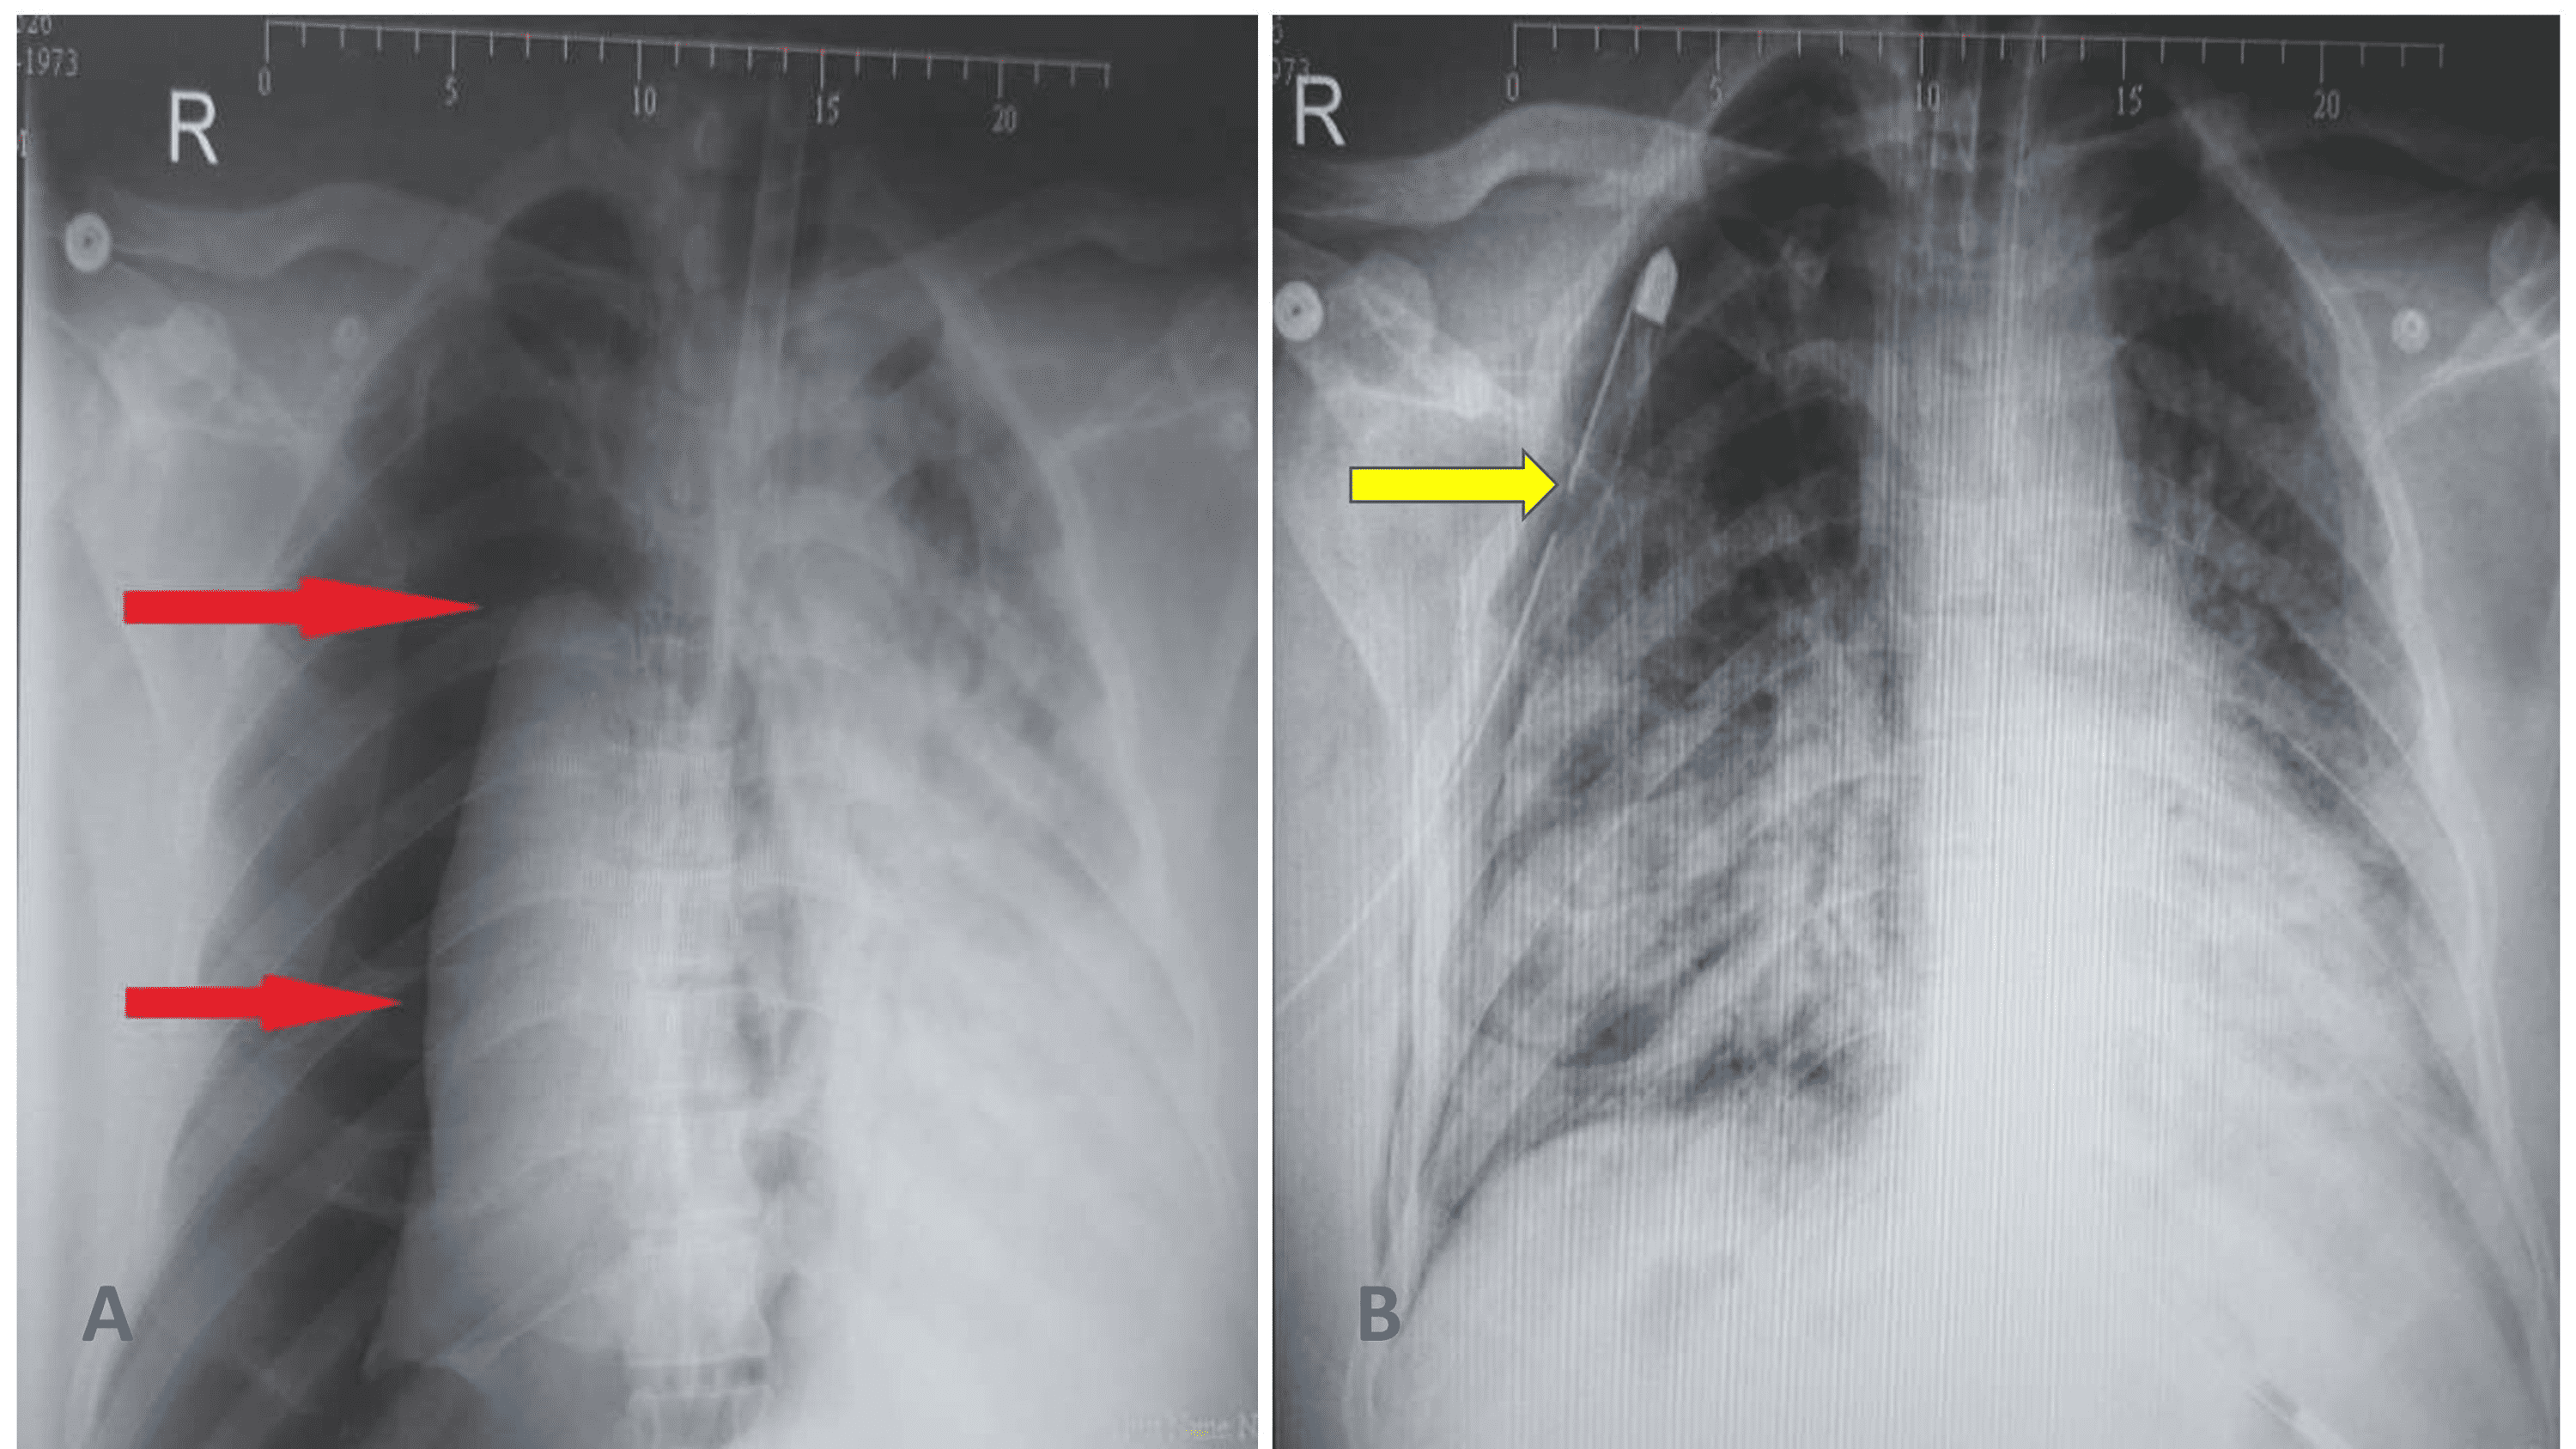

Figure 1 from Incidence of Barotrauma in COVID19 Patients Requiring Mechanical Ventilation A Hospital Bed Barotrauma Is there a way to do that? Click on the bed to get in and wait. You could also grow pom, but that's for. Also, send ppl to heal off their small injuries on beds. Beds don't heal all types of damage, according to the wiki [barotraumagame.com] the only afflictions they seem to heal are: It works but is very. Hospital Bed Barotrauma.